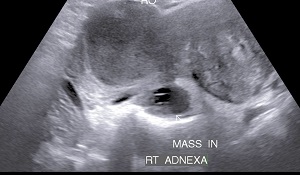

• Sonography: Sonography can confirm the disease, its extent & severity. In uterus , changes may be localized or diffuse.Its presence in ovaries lead to chocolate cyst formation. Endometriotic nodules in pouch of douglas or along walls of uterus with free fluid is a sign of advanced disease.